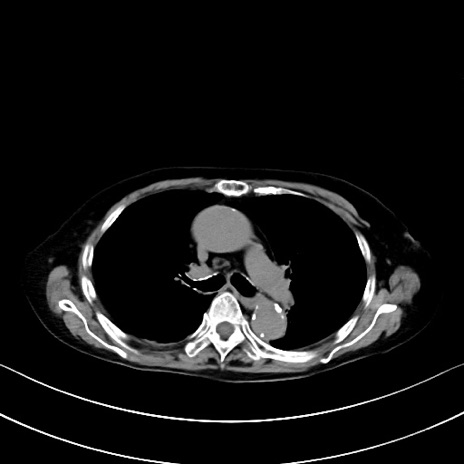

症例40(横断像)他院1日前

横断像

他院CT